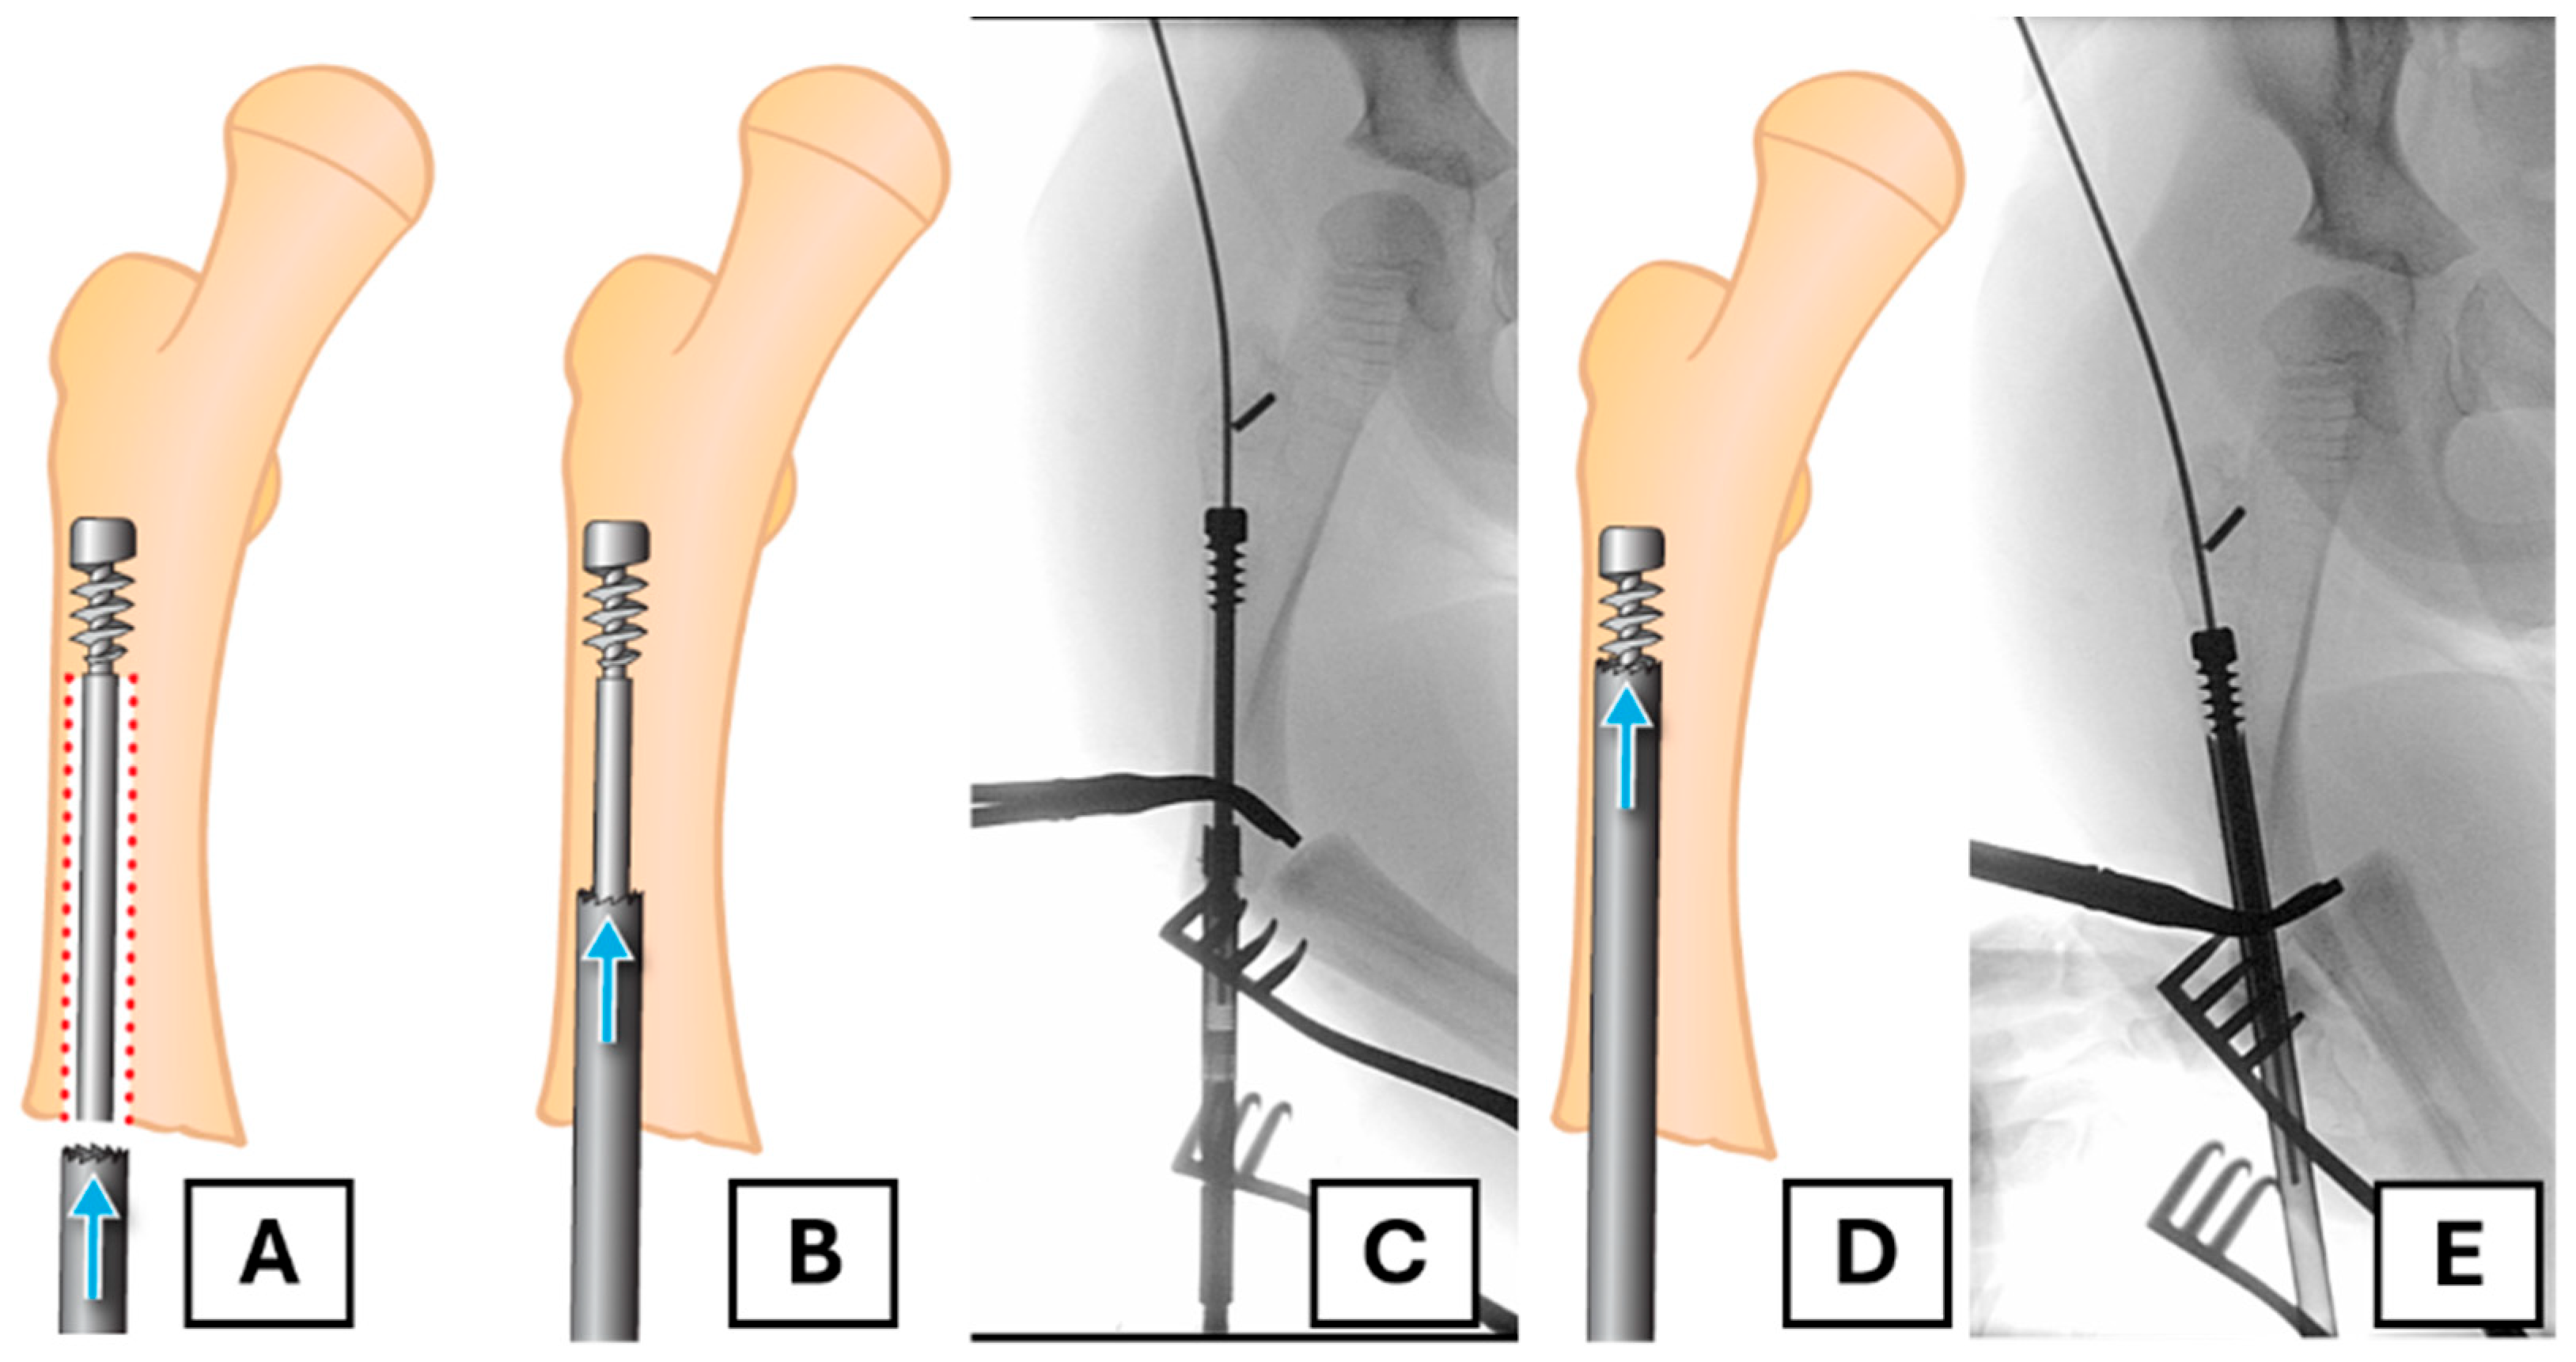

To conserve as much bone as possible and avoid coring out the head of the female component, a retrograde approach is undertaken. A suitable trephine with an appropriate diameter (e.g., 7 mm for a 3.2 mm rod) and length is placed coaxially over the end of the female component. In this case, the FD trephine of an appropriate size was missing from the rescue set; therefore, we needed to use a separate trephine (7 mm inner diameter and a thickness of 1 mm). The surrounding bone is then removed along the extent of the rod as far as the proximal fixation (Figure 3A–E).

Using a trephine that passes over the female component provides more control and limits unnecessary bone loss, ensuring that the majority of bone loss occurs ideally within the canal. Prudent use of fluoroscopy is employed throughout this process to avoid unnecessary bone removal.

Figure 3. The retrograde trephine technique for implant removal. (A) Illustration of the trephine being placed over the migrated female component. The red dotted area shows the bone to be removed (B,C) The trephine advances over the rod, removing bone from within the canal, as shown in the illustration and corresponding radiograph. (D,E) Further advancement of the trephine towards the proximal fixation, confirmed by fluoroscopy.